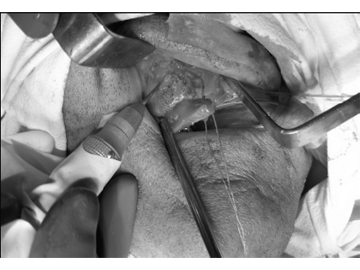

Решено произвести операцию, под общим обезболиванием: резекция области ОН верхней челюсти, ревизия верхнечелюстной пазухи справа. После обнажения кости верхней челюсти, была обнаружена четкая граница остеонекроза (рис.3). Произведена остеотомия некротизированного участка в пределах здоровых тканей (рис.4). После удаления некроти- зированного участка кости, открылось широкое сообщение с верхнечелюстной пазухой, в которой об-наружились полипозные разрастания и гной (рис.5). Были удалены патологически измененные ткани из верхнечелюстной пазухи, образовали сообщение с нижним носовым ходом, произвели тампонаду верхнечелюстной пазухи, вывели конец тампона через соустье, образованное с нижним носовым ходом. В конце, рана в полости рта была ушита наглухо (рис.6). Одновременно больному назначили антибиотики широкого спектра действия (отменили через 5 дней после операции) и местные антисептики.